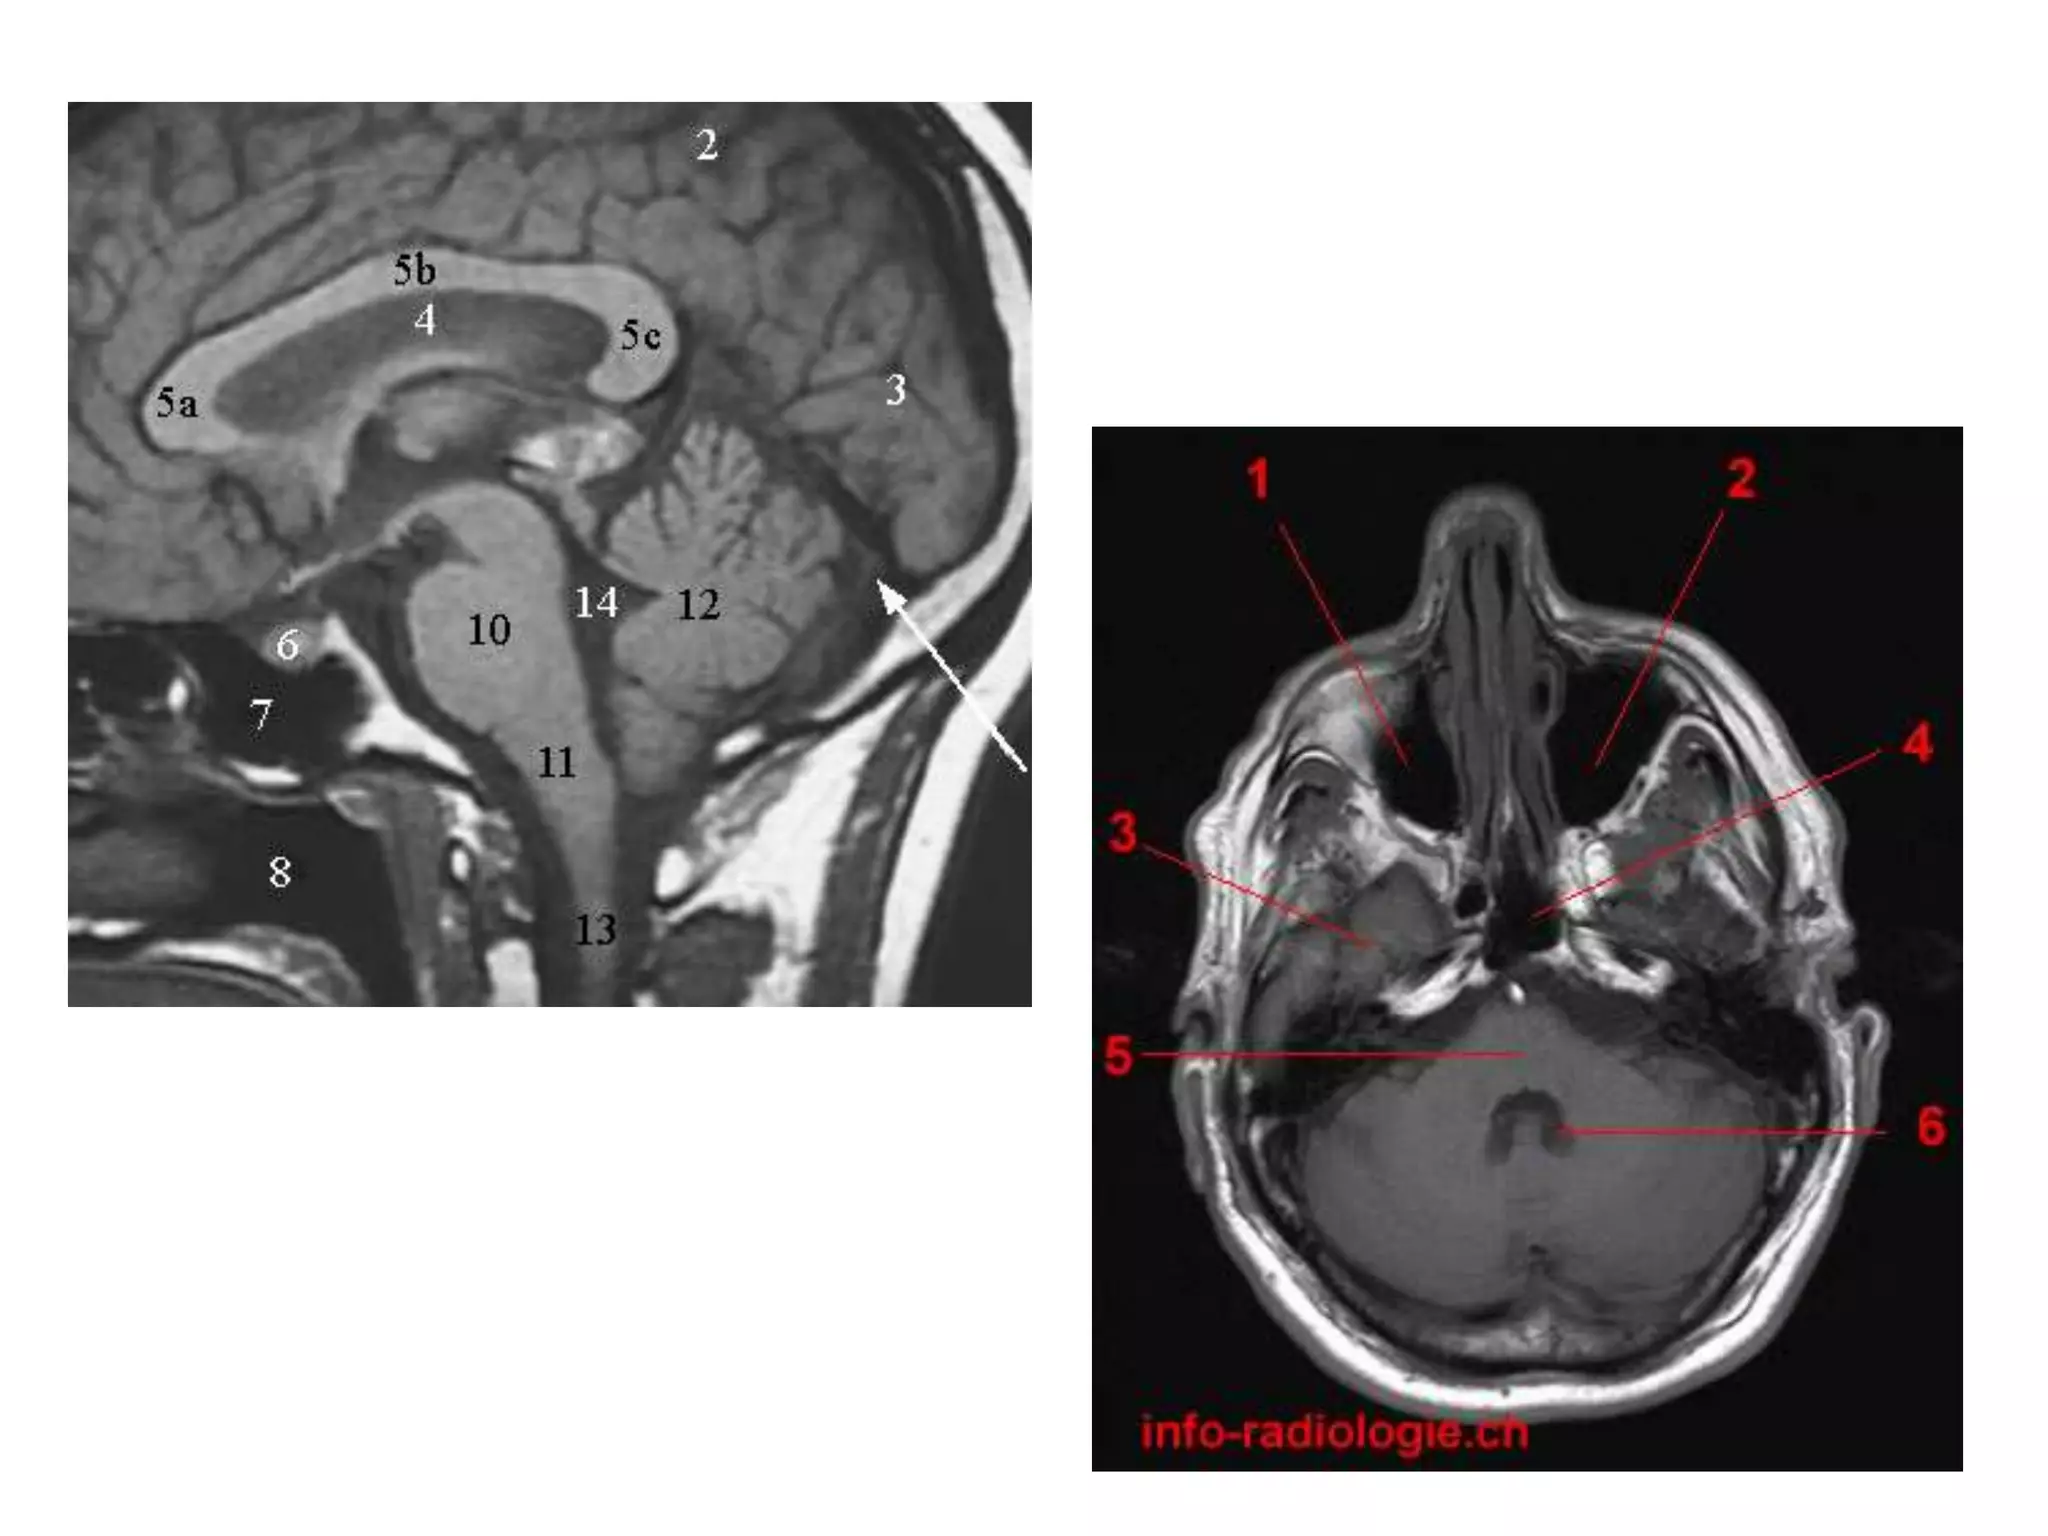

• Saggital and Coronal T1 weighted MRI – accurate

assessment of ventricles and C. callosum

• Mid Saggital section – for shape and configuration

of Aqueduct of Sylvius.

Axial MRI / CT - narrow cleft

Saggital MRI – elongated and complex curved shape

with upward, backward & downward arc.

• Radiology –

Saggital MRI: concavity that curves downward

and forward towards the floor of 3rd ventricle.

Radiology

• Axial MRI / CT – ‘kidney bean’ turned on its side.

• Saggital MRI - mid point of line drawn b/w T. sella

and trocula should intersect middle of 4th

ventricle.

• Coronal MRI – elongated rhomboid shape